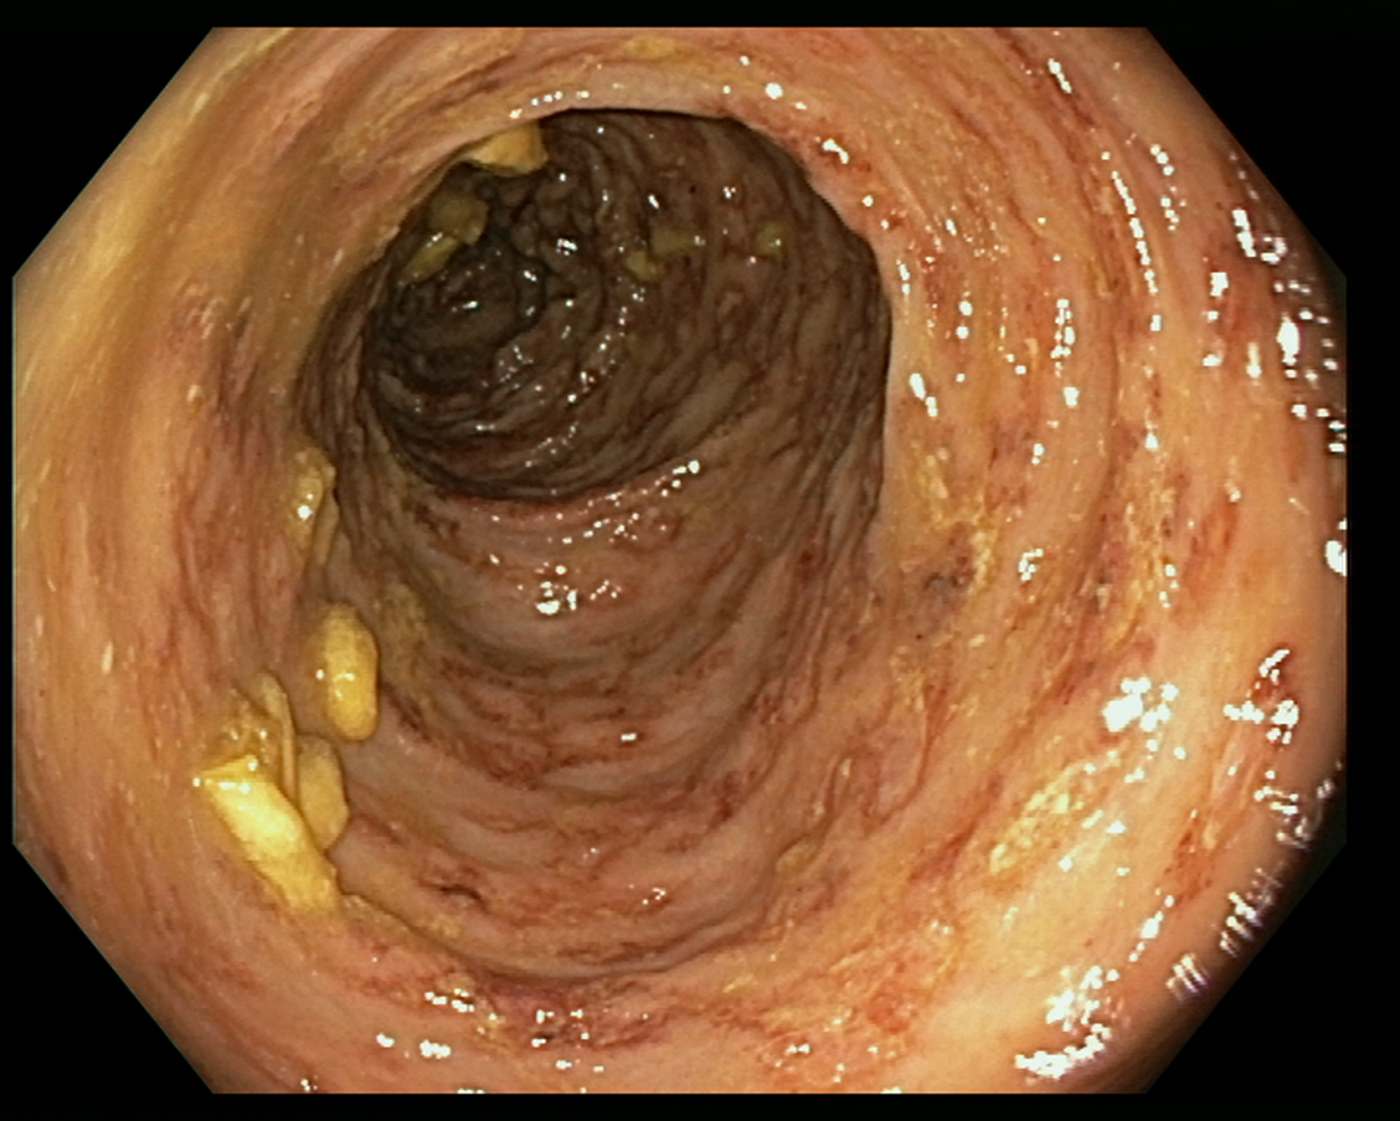

An 85-year-old patient with moderate-severe chronic renal failure, insulin-dependent diabetes mellitus with peripheral polyneuropathy, COPD, prostatic hypertrophy and rheumatic polymyalgia with probable small-vessel vasculitis was admitted to the State Hospital in San Marino on the 8 March 2017 for fever, asthenia and hyporexia. Blood tests showed hypochromic microcytic anaemia (haemoglobin 9.2 g/dl), mild eosinophilia (558 eosinophils/μl), hyperglycaemia (265 mg/dl), increased erythrocyte sedimentation rate (99 mm/h, normal values <13) and CRP (8.43 mg/dl, normal values <1). Two sets of blood culture were negative. During the first days of hospitalisation, he was kept on his usual therapy, which included prednisone 12.5 mg/day. On the 13th March a contrast-enhanced CT scan was done, showing diffuse bowel and gastric wall thickening, thickening of the bronchial walls and pulmonary interstitial oedema. A colonoscopy demonstrated a flat lesion in the right colon, intestinal inflammation, ulcers and petechial spots (Fig. 3). The histological examination revealed lymphoplasmacellular and eosinophilic infiltration, epithelioid granuloma and multiple S. stercoralis larvae (Fig. 2b). Also, intranuclear inclusion bodies compatible with cytomegalovirus (CMV) infection were found; this infection was confirmed by PCR on blood, that showed 1888 UI/l viraemia. On the 16 March treatment with ivermectin 200 μg/kg/day and piperacillin/tazobactam 2.25 g three times a day (dosage adjustment for renal failure) was started. The dose of prednisone was gradually reduced. In the meantime, also stool examination, PCR and IFAT resulted in positive for S. stercoralis. Hence, on the 20 March, albendazole 400 mg twice a day was added. The general condition of the patient gradually improved, and CMV viraemia reduced spontaneously along with clinical recovery. Antihelminthic therapy was stopped 2 weeks after negativisation of stool microscopy, that was achieved after 21 days of treatment. The patient was discharged on the 7th April, in fair clinical condition. On the 30 May, he underwent a colonoscopy that showed almost complete resolution of the inflammation. The biopsy of the flat lesion (observed also in the previous examination) demonstrated a villous adenoma.

Fig. 3. Erythematous and oedematous mucosa of the transverse colon, with aphtoid ulcers and petechiae.